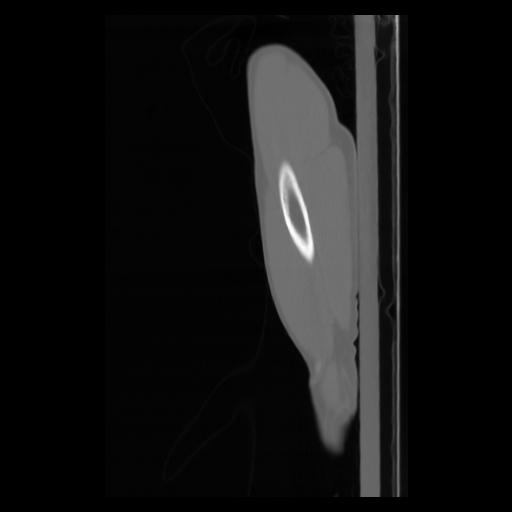

30 CUERPO,CE,Sagittal,3.000,CUERPO,Sagittal,